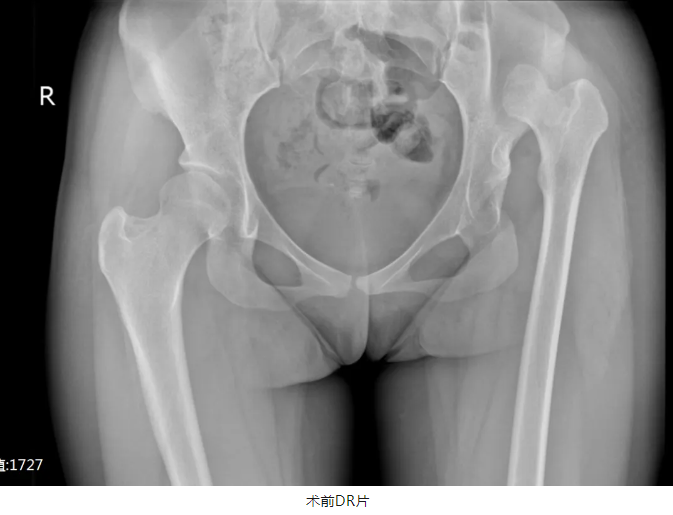

经多方寻医,小萍父母打听到海南中德骨科医院专科技术过硬,遂前来需求系统治疗。通过详细了解患者的病史并完善相关检查后,诊断为“先天性左髋关节发育不良(Crowe Ⅳ型)并左髋关节脱位”收入我院关节中心。

“先天性髋关节脱位,越早治疗,效果越好,年龄越大,治疗复杂性也越大……”接诊的医疗院长兼关节中心\运动医学科主任 付昆教授与其团队认真分析患者病情,并与国内知名专家反复讨论病历后,在征得患者及家属同意后,决定为其进行“左侧人工全髋关节置换术+左股骨近端截骨术”予以治疗。

完善术前检查及术前准备,排除手术禁忌后,付昆教授带领团队为患者实施手术,经过3个小时的精细手术操作,顺利完成髋臼和股骨头置换,关节复位,松紧及活动度良好,双侧肢体长度相等。